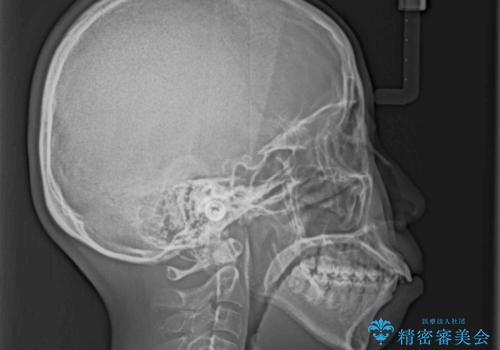

上下顎ともに前突しており、特に上顎は著しい突出感でした。

また、下顎歯列には左右差があり、非対称な抜歯が必要と判断されたため、治療は困難なものとなりました。

上下左右の小臼歯4本を抜歯し、ワイヤー装置にて口元を引っ込めるよう矯正治療を行うこととしました。